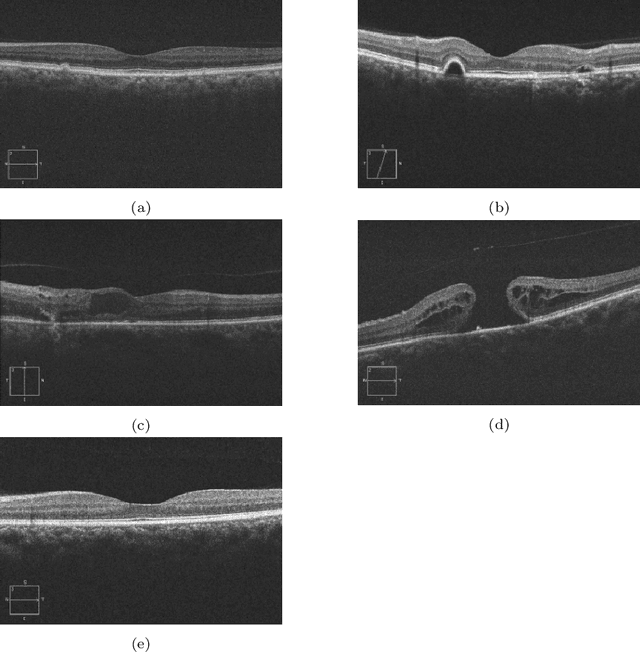

Abstract:In this technical report, we explore the use of homomorphic encryption (HE) in the context of training and predicting with deep learning (DL) models to deliver strict \textit{Privacy by Design} services, and to enforce a zero-trust model of data governance. First, we show how HE can be used to make predictions over medical images while preventing unauthorized secondary use of data, and detail our results on a disease classification task with OCT images. Then, we demonstrate that HE can be used to secure the training of DL models through federated learning, and report some experiments using 3D chest CT-Scans for a nodule detection task.